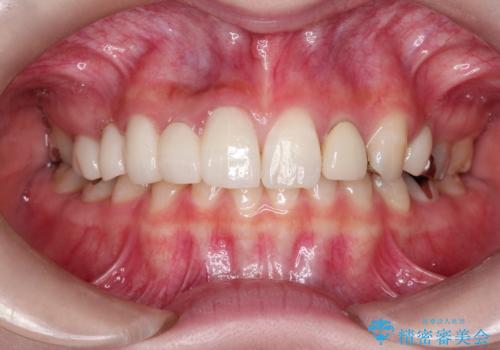

- 昔装着したかぶせ物が、不自然なのでやりかえたいとのことで来院されました。

前歯にレジン前装冠(保険内)が装着されており、自然な透明感がありません。

また奥歯にまたがるブリッジも金属のもので、適合もよくありませんでした。